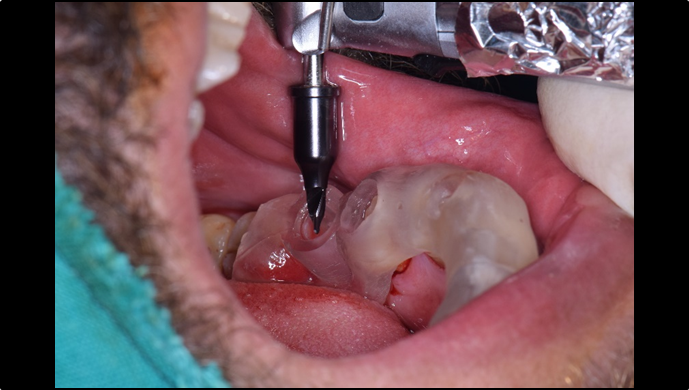

“ Immediate function recovery in the mandibular posterior with ONE-DAY implant ”

Clinical case: EImmediate implant placement & loading of #35 extraction socket with defect

- Courtesy of Dr. Kwang Bum Park, Korea -

Dr. Kwang Bum Park, immediate loading, digital guided surgery, digital ONE-DAY implant, maxillary anterior, #21, guided surgery, immediate loading, AnyRidge, R2GATE, Mega ISQ, MEG Torq, R2GATE Full Surgical Kit

implant system, R2GATE Guide, R2GATE surgical kit (AnyRidge), Mega ISQ, Mega-Oss